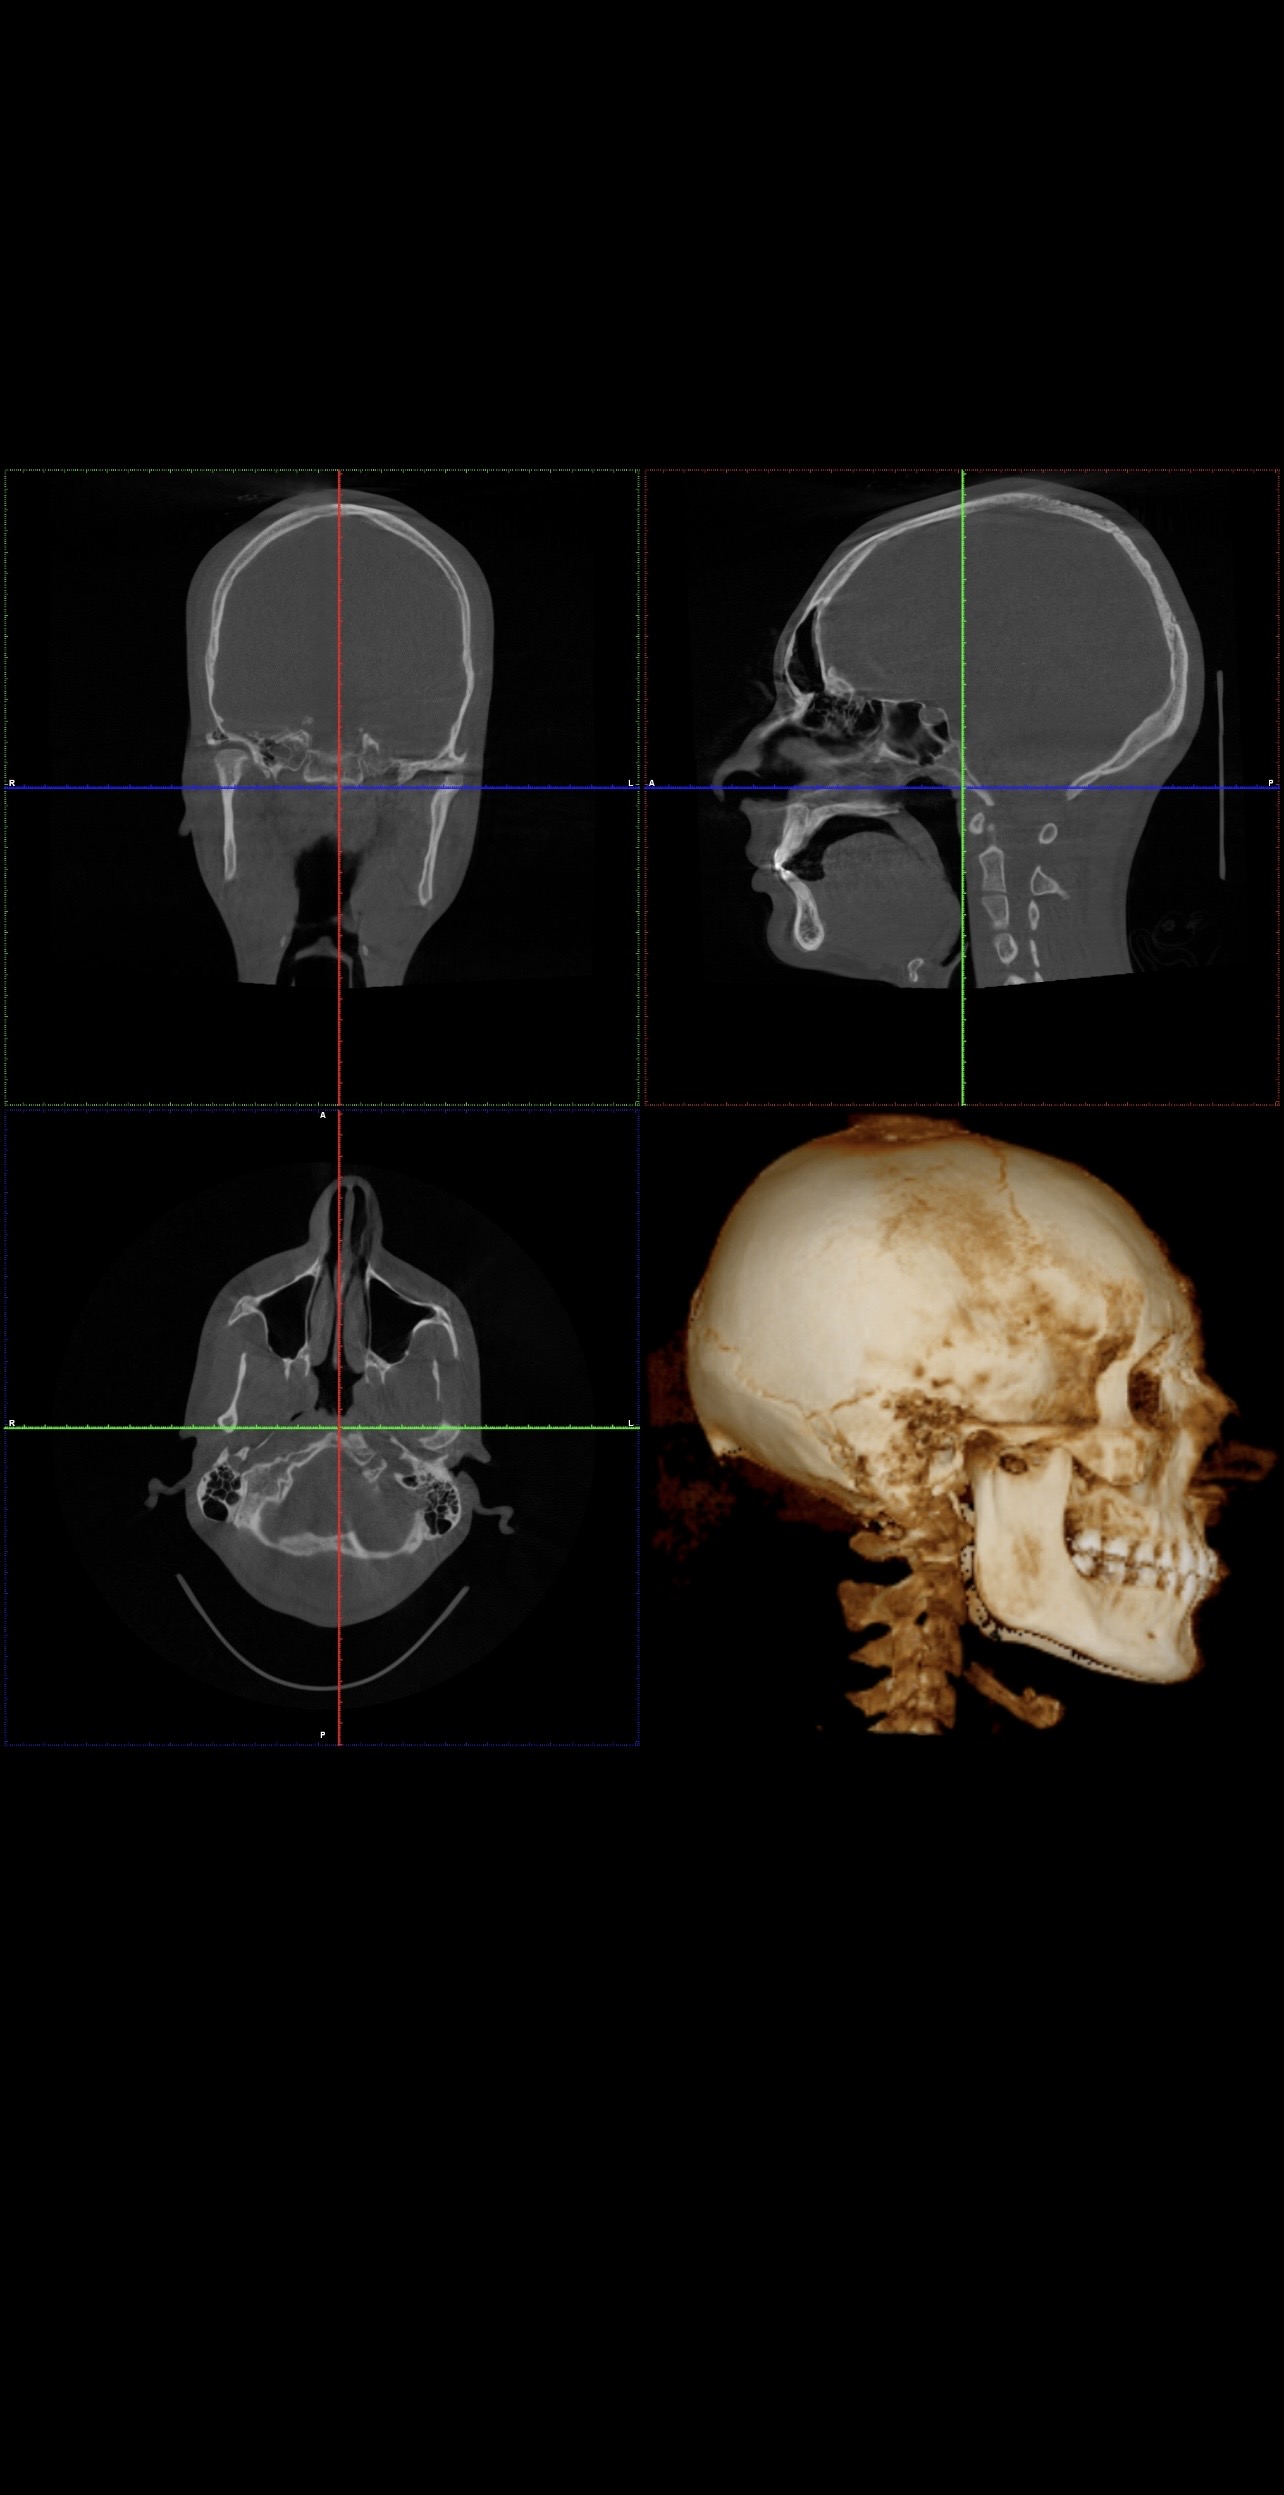

Ct scan for reference

Your mandible is recessed and your airway oropharynx cross section looks very small. Just imagine when you relax and lay down, your tongue goes back and blocks your airway even more.

Get a sleep study (preferably type 1 or 2, type 3 is bad) and consult a maxillofacial surgeon

The philtrum seems quite tall in the ct which may explain why your teeth show less. You have room for advancement in both jaws

Yes. Your lower front teeth are inclined forward